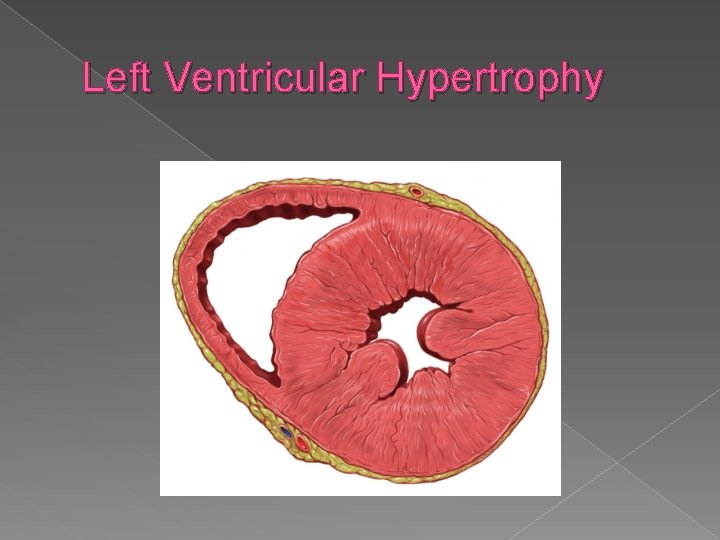

Ventricular hypertrophy › In utero - hypertrophy is most commonly associated with cardiac outlet obstruction but may be associated with maternal diabetes.

Ventricular hypertrophy

Left Ventricular Hypertrophy